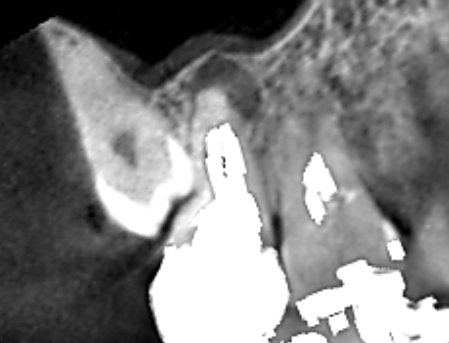

続きを読むVol.27 症状が無くても膿があることが多い!実は、根管治療の失敗の多くは自覚が無いのです。

- 上顎第二大臼歯・ 根管治療失敗例・ 歯槽骨再生・ 無症状でも膿・ 精密根管治療の重要性

治療中に他の歯に膿が見つかったケースです。他の歯の治療のためにCTを撮影したところ、上顎第二大臼…